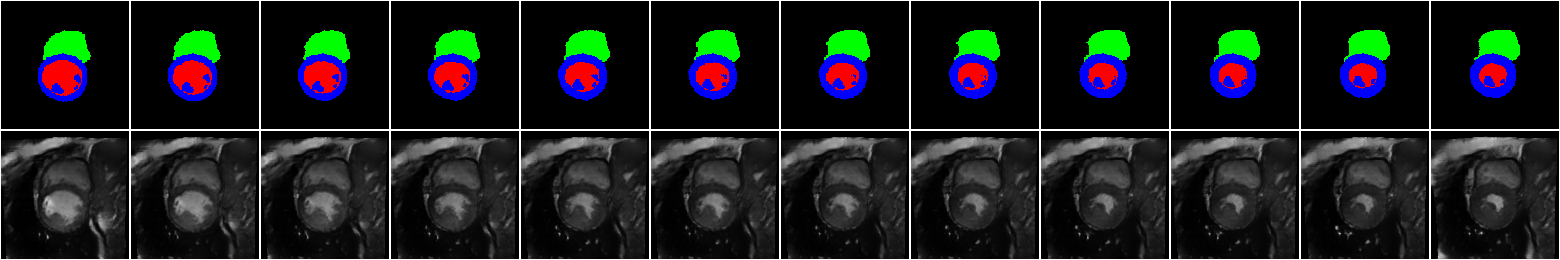

The main results, which are the synthetic images corresponding to the XCAT labels are shown in \figurereffig:synth_frame_0-12_base. For visualization purposes, we fix the location and vary the time frame. The results for 12 time frames from end-diastolic to end-systolic phase (from left to right) are shown at the base location of the short axis view of the heart. Due to limited space, similar results for other time frames and locations are shown in A, \figurereffig:synth_frame_0-12 and \figurereffig:synth_frame_12-24. Additionally, a 4D visualization of our results is available here: \urlhttps://bit.ly/2REVAzB. As seen in these figures, for a fixed location, the classes of interest are generated according to the input label map, while the background is consistent and coherent.

fig:synth_frame_0-12_base

Figure LABEL:fig:synth_frame_0-12 shows the generated samples for XCAT labels for 12 time frames from end-diastolic to end-systolic phase while fixing the location. \figurereffig:apex_0-11, 6 correspond to apex and middle locations respectively.

fig:synth_frame_0-12

\subfigure[The apex location][c]

\subfigure[The mid location][c]